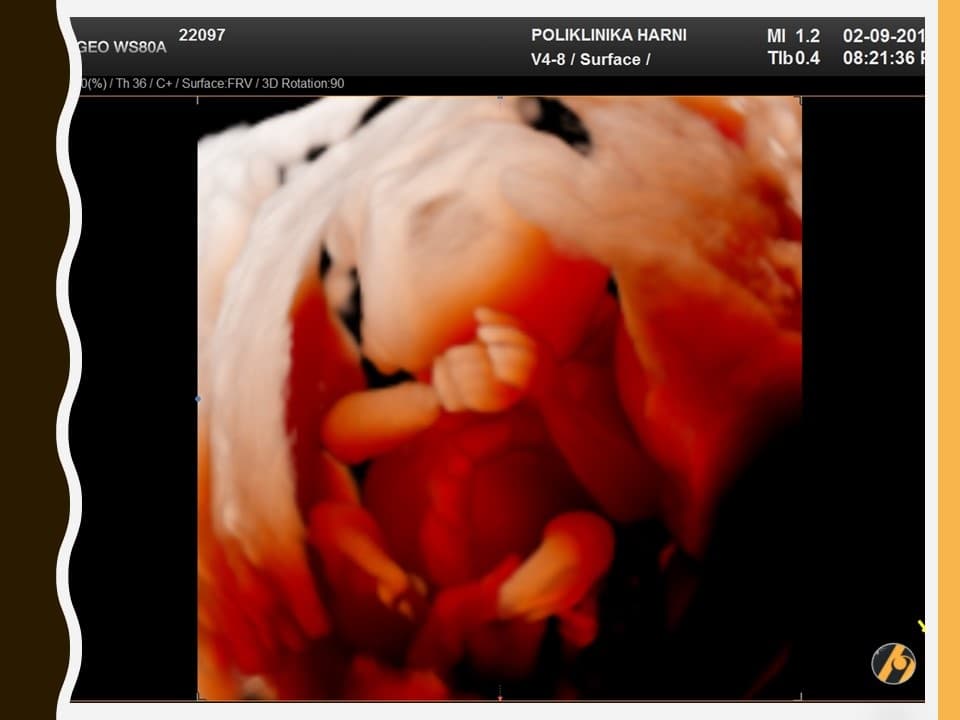

Lice vaše bebe sve je razvijenije. Prepoznaju se korijen nosa, formirani su obrazi, uši su sa strana na vratu prema glavi, a oči su sve bliže jedno drugome. Štitna žlijezda dovršila je svoj razvitak i spremna je za početak stvaranja vlastitih hormona.

U ovom tjednu dolazi do nicanja finih lanugo dlačica koje rastu gotovo po cijelom tijelu fetusa. Vjeruje se da lanugo dlačice imaju zaštitnu ulogu, prije svega pridržavajući verniks na površini kože. Vernijs je masni, voštani i sirastog izgleda pokrov kože koji beba sama izlučuje i stvara.

Lanugo dlačice otpadaju, a vernix većim dijelom iščezava prije nego što će se beba roditi. Zajedno s lanugo dlačicama pokazuju se obrve, za sada veoma nejasno, čak niče i po koja vlas na glavi. Mišići lica se počinju kontrahirati, pa se nalicu mogu vidjeti grimase i zijevanje. Ispod zatvorenih očnih kapaka počinju se pokretati oči.

Vaša beba dugačka je 8.0 - 11.0 cm, a teška 30 - 60 g.